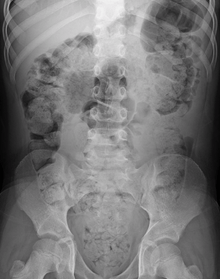

| Constipation in a young child as seen by X-ray. Circles represent areas of fecal matter (stool is opaque white surrounded by black bowel gas). | |

During physical examination, scybala[24] (manually palpable lumps of stool) may be detected on palpation of the abdomen. Rectal examination gives an impression of the anal sphincter tone and whether the lower rectum contains any feces or not. Rectal examination also gives information on the consistency of the stool, the presence of hemorrhoids, admixture of blood and whether any tumors, polyps or abnormalities are present. Physical examination may be done manually by the physician, or by using a colonoscope. X-rays of the abdomen, generally only performed if bowel obstruction is suspected, may reveal extensive impacted fecal matter in the colon, and confirm or rule out other causes of similar symptoms.[7][8]